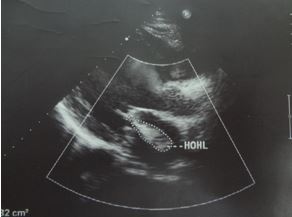

+ Siêu âm tim: Buồng thất trái giãn, chức năng tâm thu thất trái giảm. Hở hai lá nhẹ; hở chủ nhẹ, tăng áp lực động mạch phổi nhẹ. EF 37%.

Hình 3. Hình ảnh siêu âm tim